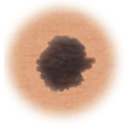

Skin cancer showing more than one color.

Color

When the mole has more than one color